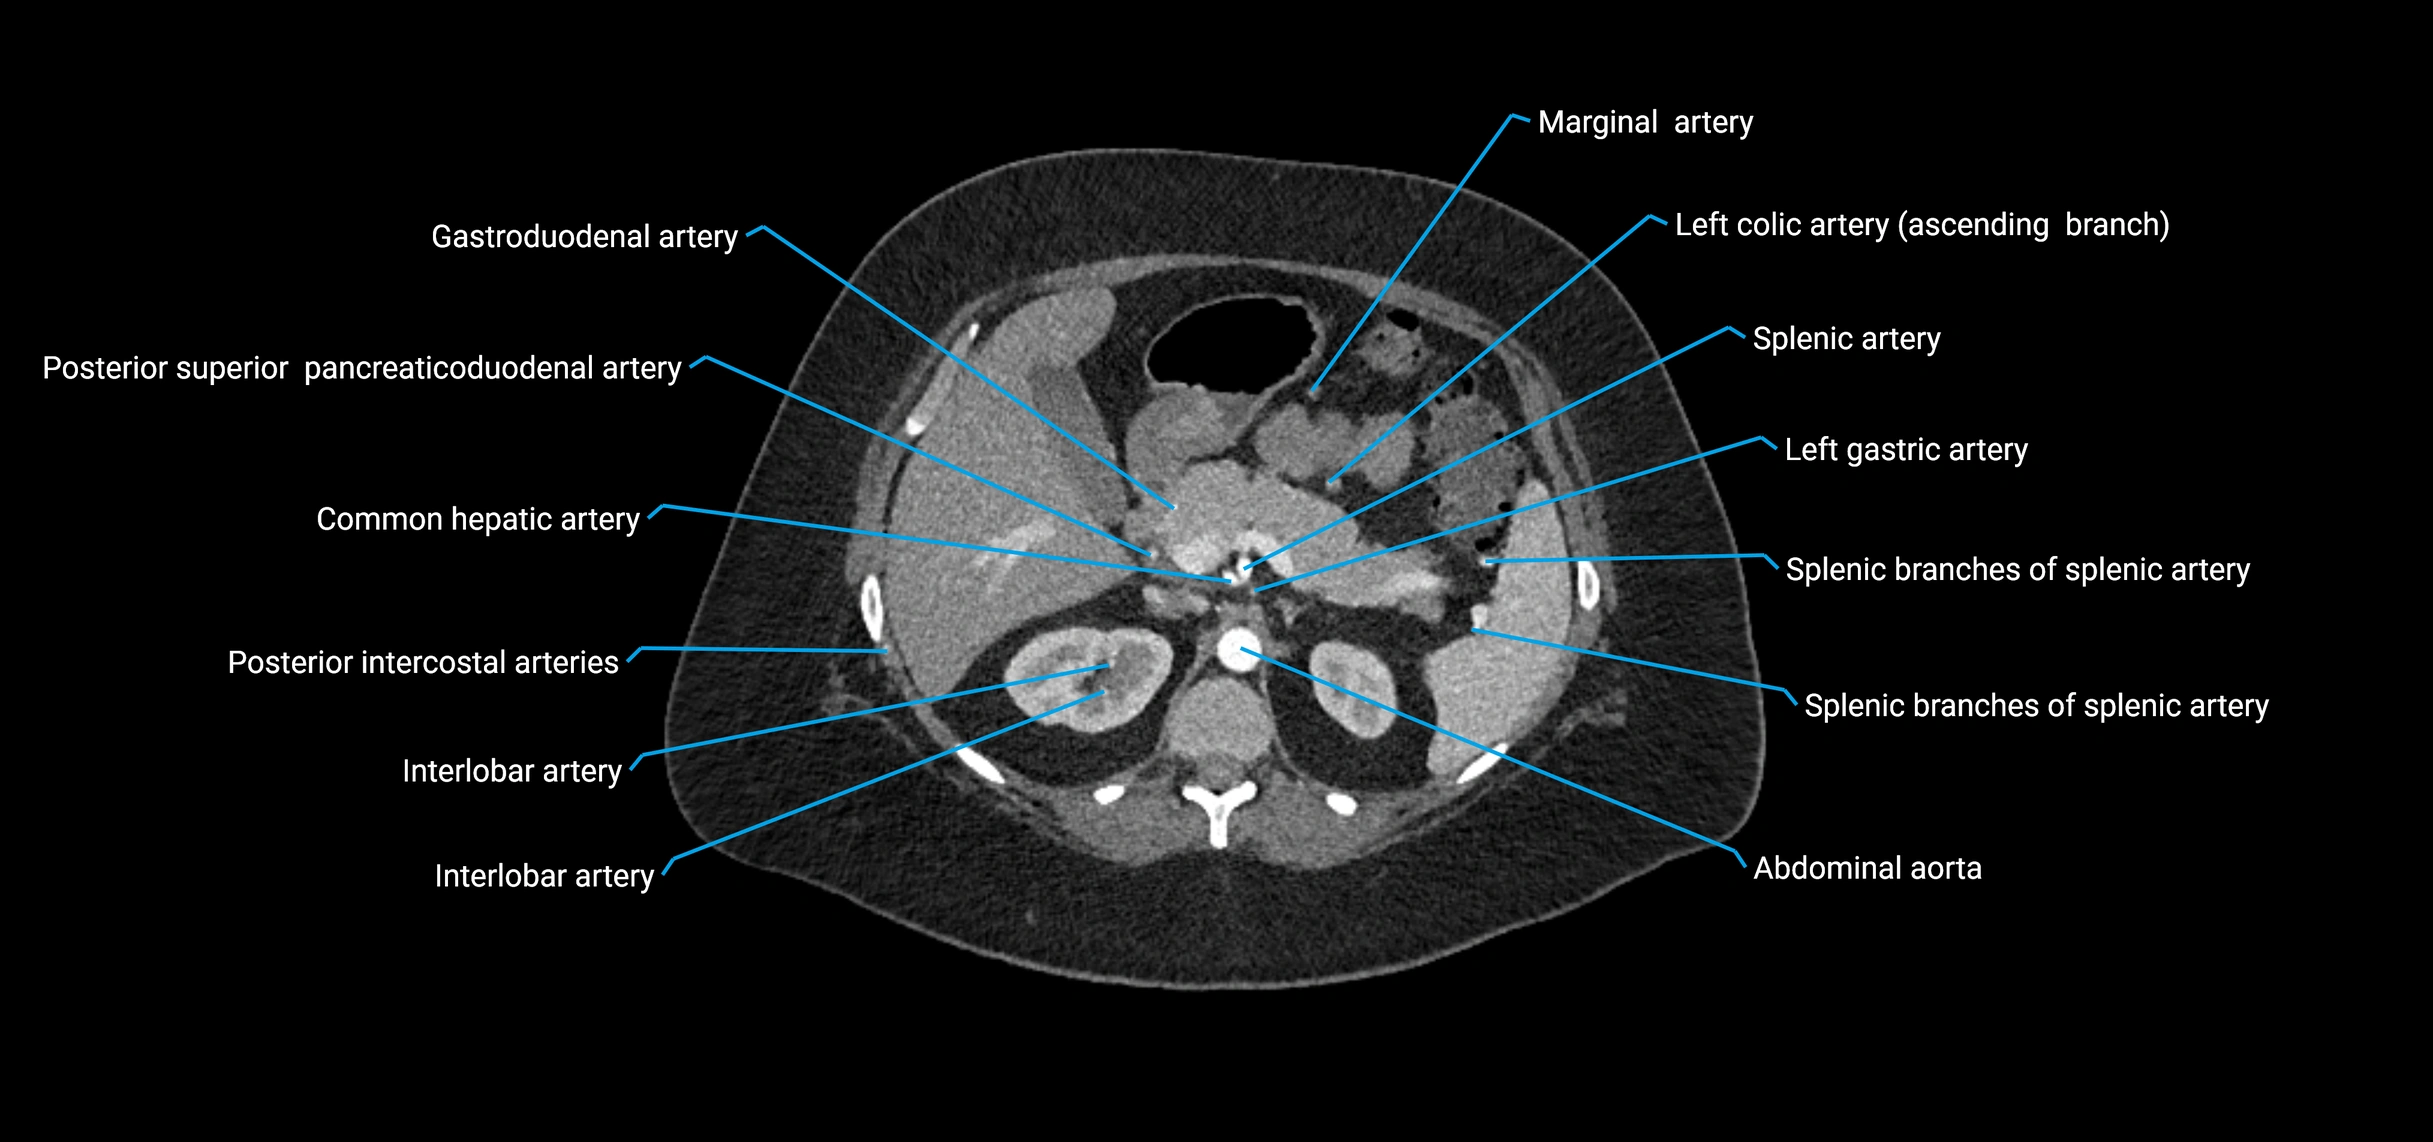

CT Appearance

Non-contrast CT:

• Appears as a tubular soft tissue structure anterior to vertebral bodies

• Calcified atherosclerotic plaques appear as hyperdense foci along the wall

• Useful for screening abdominal aortic aneurysm (AAA) size and mural calcification

Contrast-enhanced CT (CTA):

• Gold standard for abdominal aortic imaging

• Provides excellent detail of lumen, wall, aneurysm, thrombus, and branch vessels

• Multiplanar and 3D reconstructions help in aneurysm measurement, stent graft planning, and dissection evaluation

• Detects acute rupture, traumatic injury, or occlusion with high sensitivity

CT images

image